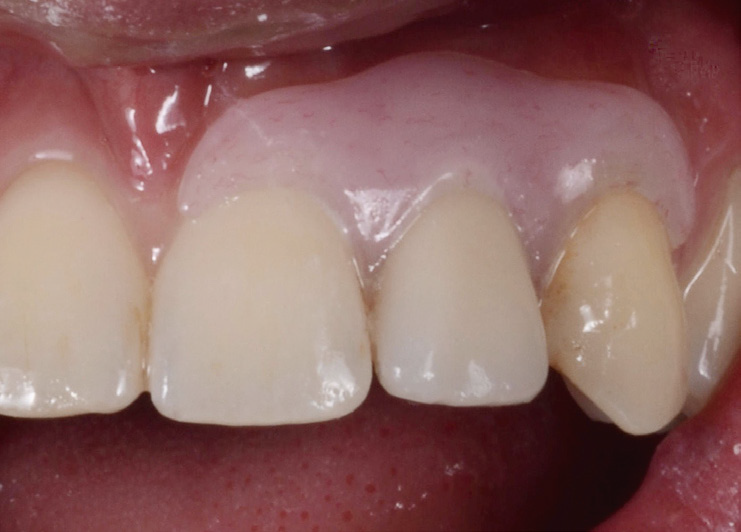

Pontic site developed.